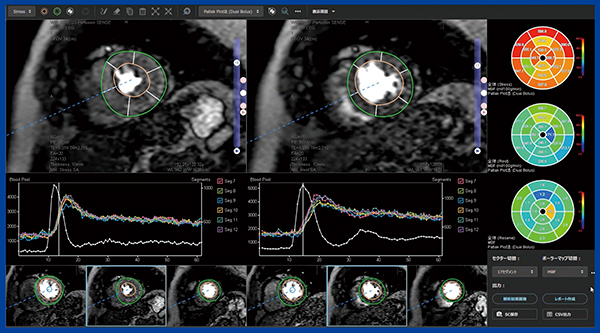

REVORASでの定量解析では,希釈検査データと安静時,負荷時のデータを読み込むと,20秒程度で自動的に安静時,負荷時の内膜縁と外膜縁がトレースされる。トレースの精度は高く,各フェーズを確認すると高い追従性を有していることがわかる。次いで,希釈検査データにROIを指定し,飽和補正に利用するTICを取得する。そして解析ボタンをクリックすると,短時間で心筋血流解析の結果を得られ,ポーラーマップ表示によるMBFと,TIC,セグメントごとのTICが表示される(図3)。解析結果は心筋全体だけでなく,心筋を内膜側,外膜側に分けたデータも切り替えて表示することができる。

図3 REVORASによる心筋パフュージョンMRIの定量解析結果